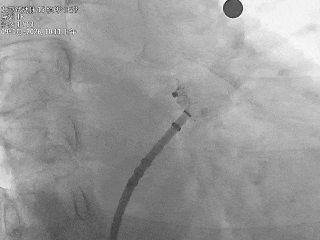

房间隔穿刺

房间隔靠后靠下进行穿刺后造影确认穿刺位点合适

术中DSA肝位造影

心耳呈菜花状,梳状肌发达

心耳内无血栓

开口32.2mm,深度超过22.4mm